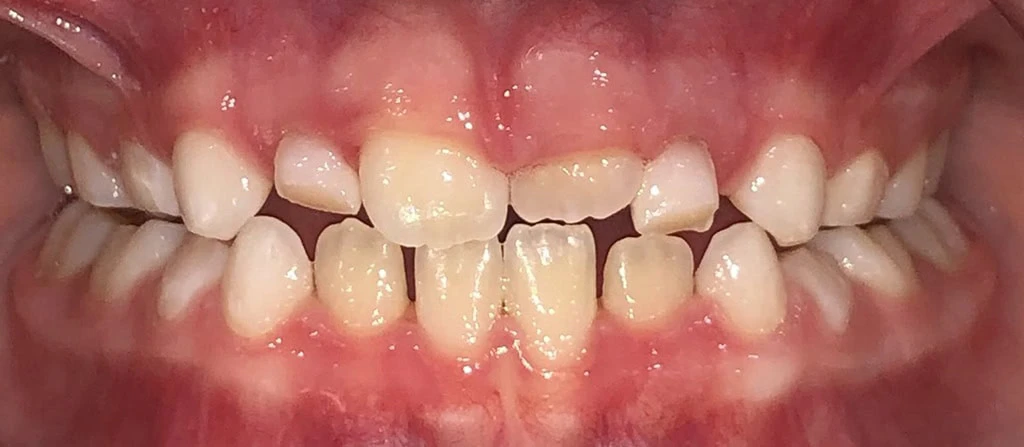

Actual Patient: Kai

Kai Before 5 Kai After 5

Severe Crowding, Traumatic Bite, Severe Deep Bite

Kai before 1 1 Kai after 1

Front View

Top View

Right & Left Sides